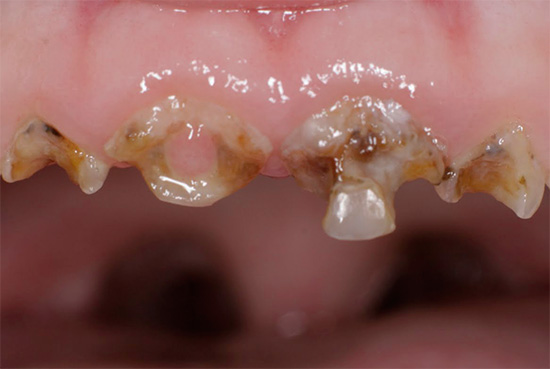

E questa foto mostra un altro esempio di come i denti sono stati colpiti carie generalizzata. Questa è una forma molto pericolosa della malattia, che minaccia una persona con la perdita di una parte significativa dei denti, la depulpazione (rimozione dei nervi) e l'installazione di corone:

Nell'aspetto e nella natura del corso, la carie delle bottiglie è quasi generalizzata. La principale differenza tra queste malattie è l'età delle persone che colpiscono: la carie in bottiglia si sviluppa principalmente nei bambini da 1 a 3 anni. Questo è spesso associato a un'immunità indebolita e malattie somatiche in tenera età.

Immagini della bottiglia della carie: